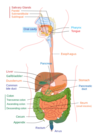

Identify the following structures of the Digestive System:

- Oesophagus

- Stomach

- Duodenum

- Jejunum

- Ileum

- Caecum

- Ascending colon

- Transverse colon

- Descending colon

- Sigmoid colon

- Rectum

- Anus

- Pancreas

- Liver

- Spleen

Identify the following structures of the Urinary System:

- Right and left kidneys

- Ureters

- Bladder

- Urethra